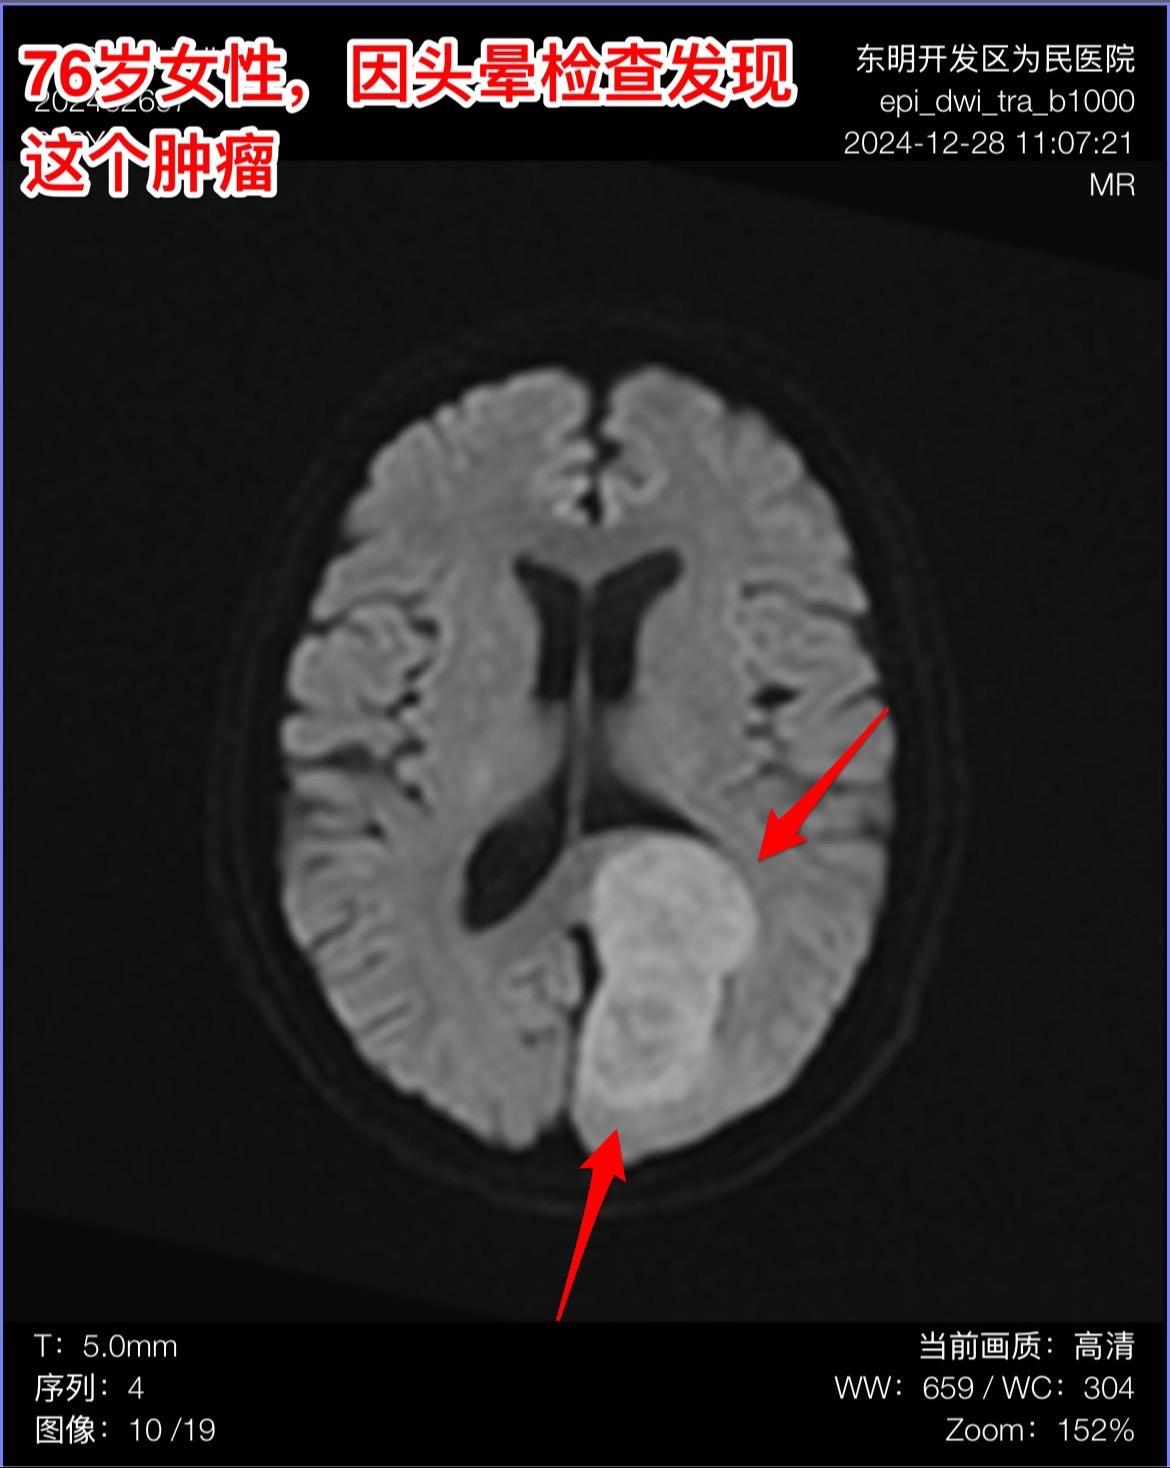

76岁女性,发现脑肿瘤需要作手术吗?山东省菏泽市的76岁女性,因头晕症状到医院去 头部磁共振检查,结果发现脑部长了一个大肿瘤,见图。 家人急切地想知道:是不是要立即动手术? 病人两年前还作过乳腺癌手术和甲状腺肿瘤切除手术。还有糖尿病病史20年。体重只有八十来斤。 这个老人需要立即作手术吗? 我看磁共振照片后印象是脑膜瘤。鉴于病人的身体状况不好,高龄,症状也不重,我建议先观察一段时间,不急于作手术。 朋友们,你们的意见是什么?